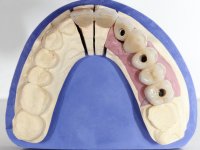

The patient was proposed to undergo a fixed oral rehabilitation consisting of a 2-element bridge over teeth 11 and 21 and a 5-element bridge over 3 implants that would be placed in the location of teeth 22, 24 and 26. The prosthetic structures would have an infrastructure in Zr coated with ceramic and the bridge over the implants would be screwed. The indicated extraction of teeth 25 and 26 and placement of an implant in the 26 site would imply surgery to fill the maxillary sinus. As the patient showed interest in having fixed temporary rehabilitation during treatment, we divided the treatment into 6 phases to achieve this goal: 1- Placement of a temporary bridge over teeth 11,21,25 and 26. With tooth extraction 24. 2- Placement of 2 implants in the location of teeth 22 and 24. 3- Placement of a temporary 6-element bridge over teeth 11 and 21 and over the implants. 4- Carrying out surgery to fill the maxillary sinus. 5 – Placement of the implant in the location of tooth 26 and in the area where the filling of the maxillary sinus was made. 6 – Placement of the definitive work.

A temporary acrylic bridge made in the laboratory with 7 elements was made, with teeth 11,21, 25 and 26 as pillars. The old bridge was removed and tooth 24 was extracted. The provisional bridge after relining was cemented in the mouth. Two implants were placed in the teeth 22 and 24 and 3 months after this intervention an impression was made to make a temporary bridge screwed over the implants and cemented to the teeth. The bridge was placed in the mouth and teeth 25 and 26 were extracted. 3 months later, surgery was performed to fill the maxillary sinus and 6 months later the implant was placed in the location of tooth 26. After osseointegration of this implant, the final impression was made for the final work. The bridge over the implants was permanently screwed on and the bridge over the teeth was cemented with resin-reinforced glass ionomer cement.